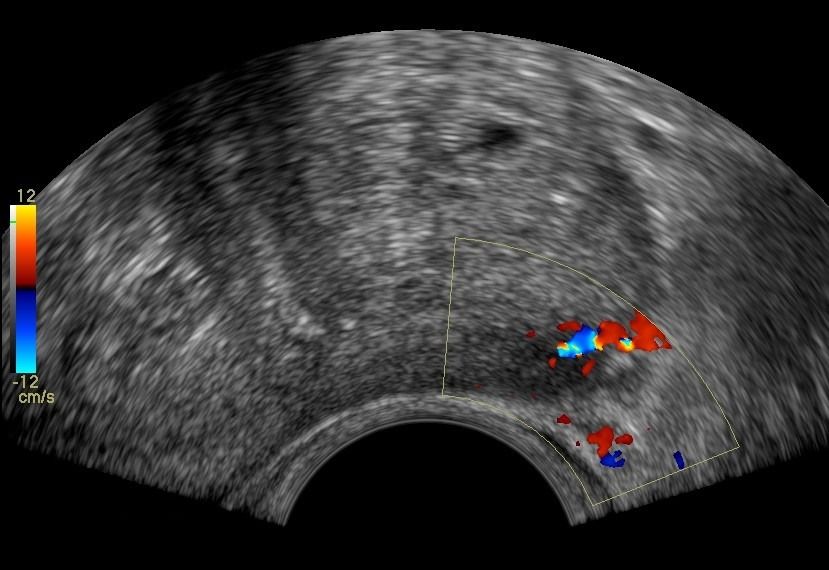

- Peripheral Prostate Zone: The exam can detect focal lesions, such as neoplasms, in the peripheral zone of the prostate.

- Central Prostate Zone: The central zone can be checked for the presence of inflammation, abscesses, calcifications, or other space-occupying lesions.

The Transrectal Ultrasound provides more information about the size, morphology, and focal lesions of the prostate compared to the lower abdominal ultrasound. As a specialized examination, it is performed when there are clinical and biochemical indications, such as elevated PSA (prostate-specific antigen).